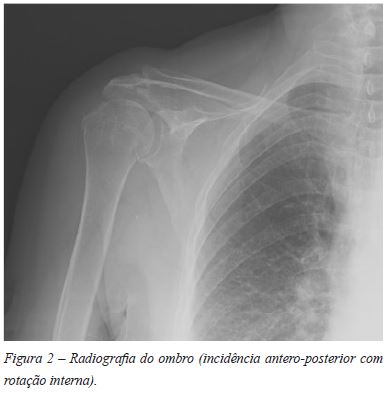

Ao RX esta entidade geralmente passa despercebida, sendo estes geralmente normais. Por vezes podem mostrar derrame articular, edema dos tecidos moles ou destruição extrínseca associada a esclerose5.

Mulher de 74 anos, antecedentes pessoais irrelevantes. Enviada à consulta de Ortopedia por omalgia direita com um ano de evolução, sem história de trauma. Ao exame objectivo apresentava dor com a mobilização articular e limitação marcada do arco de movimento, sem massas palpáveis ou sinais inflamatórios. Não apresentava déficies neurológicos. O RX do ombro foi normal (Figuras 1 e 2).